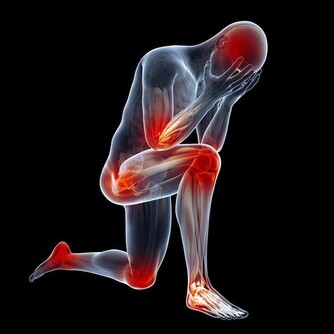

喝酒臉紅並不是因為這個人有多能喝,反而因為他特別不能喝,臉紅就是一種“警告”。

而喝酒臉紅正是因為體內缺乏將乙醛轉化為乙酸的酶,

導致乙醛在體內蓄積,損害肝臟功能,增加肝病風險,長期飲酒也會導致食道癌的發生。